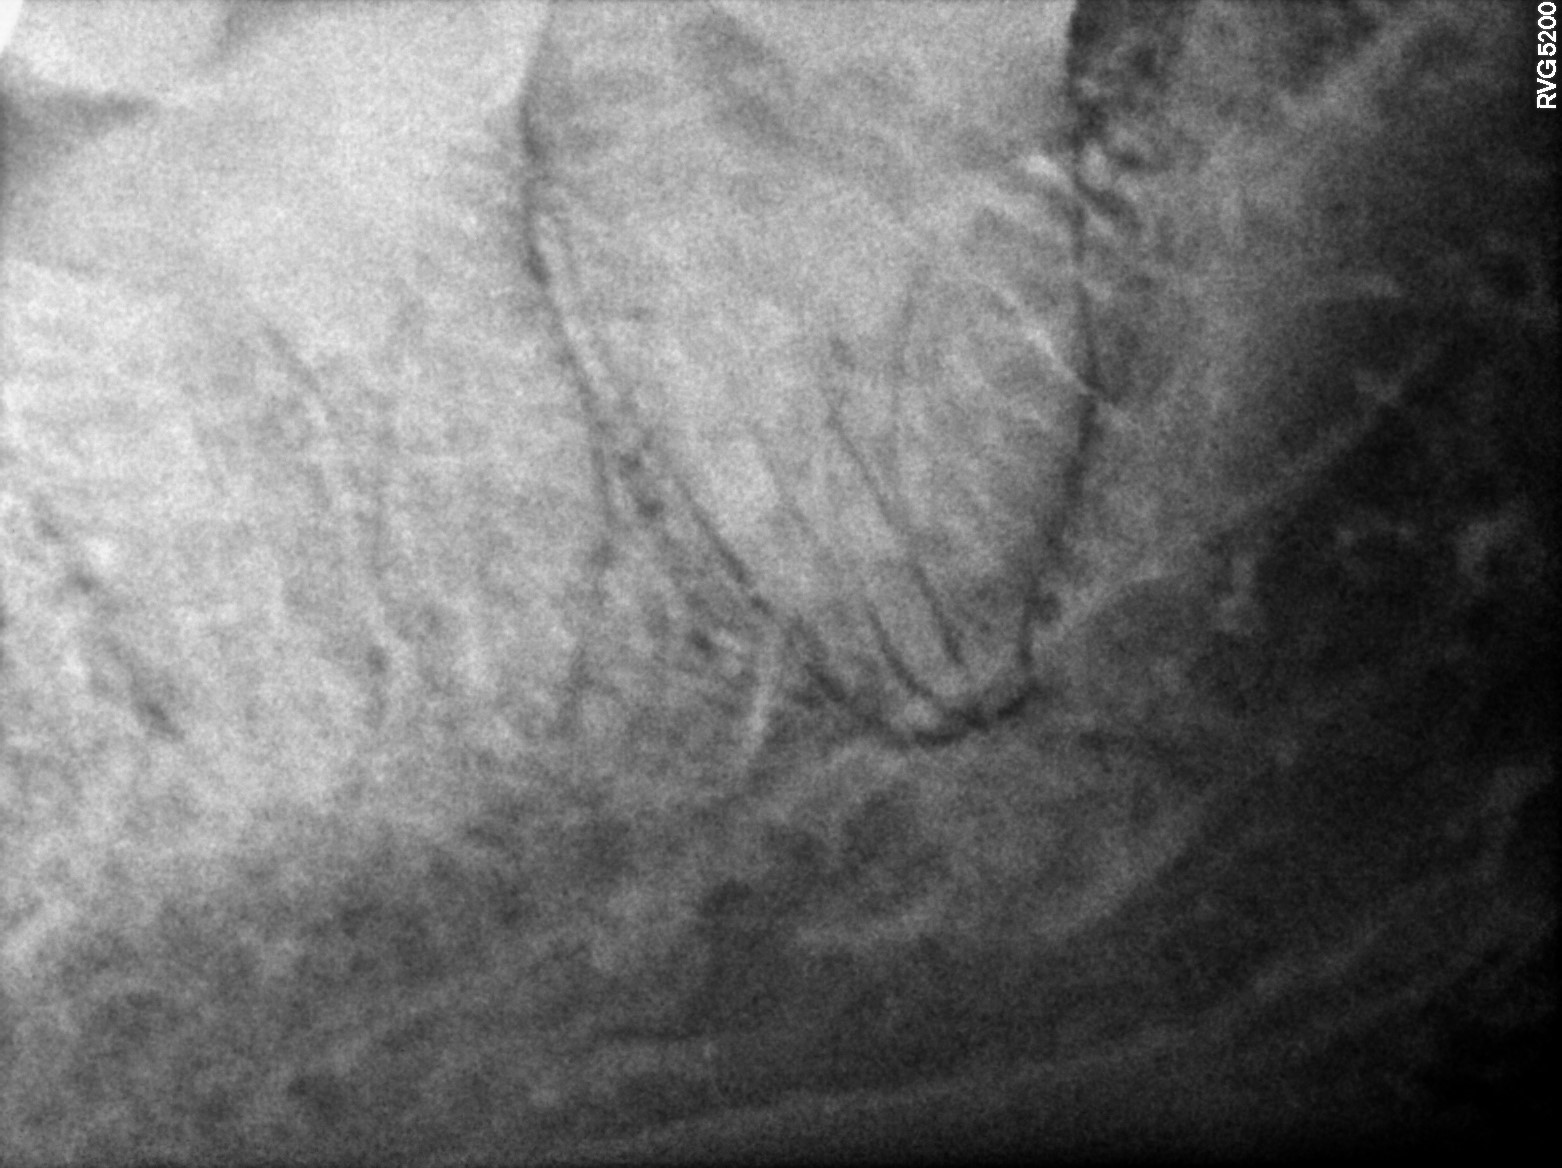

Dental Radiographs FHIR: DocumentReference · LOINC 24641-7

R55.jpg

24641-7